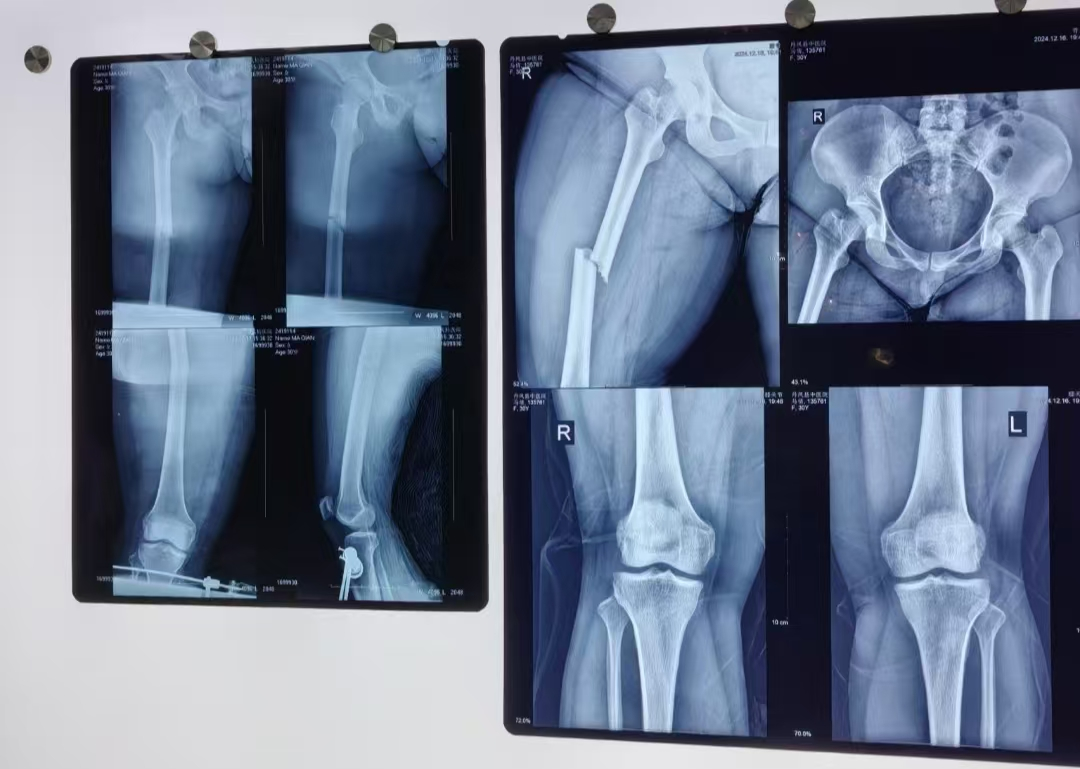

近日,在多学科团队的护航下,丹凤县医院副院长程涛、骨二科副主任李静宏及副主任医师何正位带领团队克服重重困难,成功为一名体重高达280斤的重度肥胖患者实施了股骨干骨折闭合复位髓内钉术。

患者王某,30岁,体重近280斤,走路时不慎跌倒致左股骨干骨折,由于体重太重,其他几家医院均表示医疗条件无法实行手术,于是慕名来到我院骨二科寻求进一步诊治。接诊后,骨二科副主任李静宏表示:“为这样一位“重量级”患者实施手术,对医生和患者本人来说,无疑是一场巨大的考验”。

采取何种手术方式是一大难题,程涛院长介绍,如果采用传统的股骨干手术,切口长约15cm,创口大。王某体重达280斤,皮下脂肪厚,术后极易出现脂肪液化、切口感染、骨不连等严重并发症。综合各项因素后,进行多次术前讨论,研究手术预案,最终选择为股骨干骨折闭合复位髓内钉术,这样的创口小,恢复快,同时降低了术中和术后感染发生率,而且瘢痕也小,外观更美观。

为确保手术万无一失,术前,骨二科与手术室、麻醉科对患者病情进行充分讨论,制定了周密的手术和麻醉方案。手术过程和术前预料的一样困难,仅仅摆放体位就用了大约30分钟,切开皮肤后脂肪层有8cm厚,患者的肌肉也比较粗壮,切开皮肤后十几厘米都看不到骨头,术中由2位医生轮流抱着病人的患肢,才保证手术的顺利实施。骨折复位后需要用床边透视机检查骨折复位情况,因为患者体胖,拍摄正侧斜位片时很难把机器摆放到合适的体位,要不停地升降手术台才能完成。最终,由程涛院长、李静宏主任、何正位副主任医师勠力同心,历时2小时,顺利为患者完成了手术,术中X线片显示骨折解剖复位、固定可靠,手术十分成功。术后一周,患者伤口恢复良好,可扶助行器下床行走,目前,患者已顺利出院。![]()